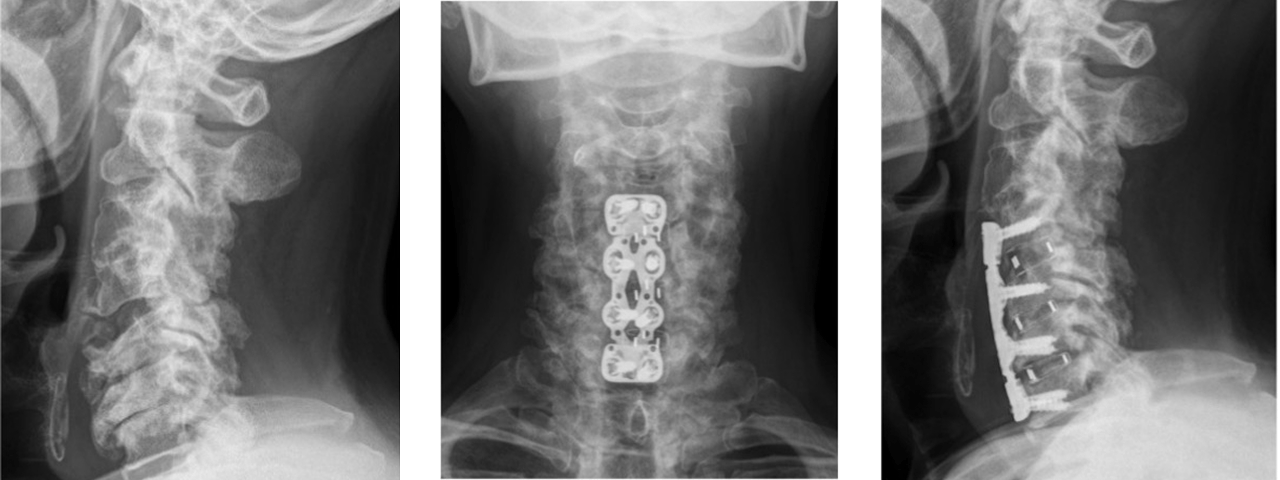

前方除圧固定術

突出した椎間板や骨棘を前方から除去して固定

いずれの方法も顕微鏡下手術を用い、安全で確実な手技を行っています。

椎間板を摘出し、チタンケージや人工骨で固定

人工椎間板置換術

若年者で可動性を保ちたい場合に適応

当院では顕微鏡下手術を標準化し、切開を最小限にして神経の損傷を防いでいます。